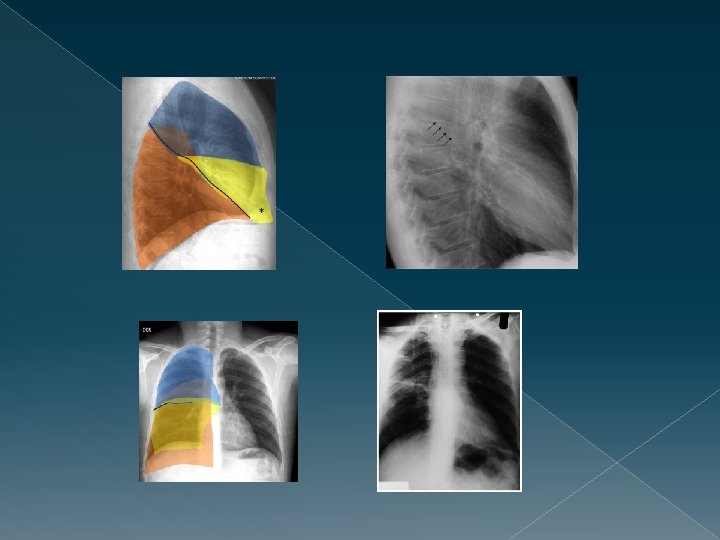

¿Y para qué nos sirve? Podemos localizar las lesiones Infiltrado Contorno que borra � Lóbulo medio derecho Borde cardíaco derecho � Língula Borde cardíaco izquierdo � Lóbulo inferior derecho Hemidiafragma derecho � Lóbulo inferior izquierdo Hemidiafragma izquierdo, aorta descendente Borde � Lóbulo superior derecho traqueal derecho, botón aórtico � Lóbulo superior izquierdo Aórta descendente proximal

Signo de la silueta - Condensación que no borra el contorno cardíaco, lo que indica la localización posterior, neumonía en LII.

Signo de la silueta+ Condensación pulmonar en la base izquierda, que borra el contorno cardiaco, que indica que la localización anterior (língula) de la lesión.